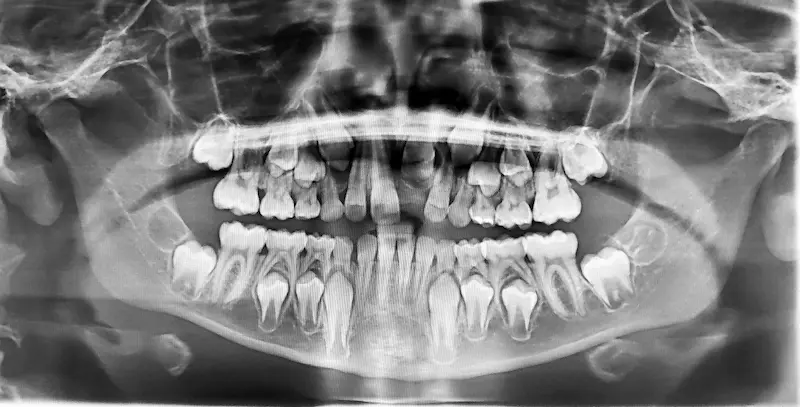

Some problems hide beneath the gums or between teeth. X-rays allow us to check for issues early — before they become painful or expensive to treat.

Yes. They offer clearer images, lower radiation, faster results, and improved accuracy.